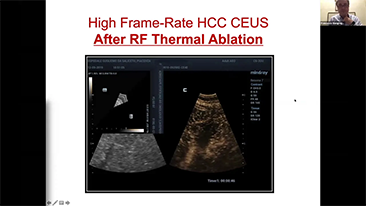

Com que clareza vocĂȘ consegue ver um fĂgado?

Para les?es hepĂĄticas focais, tais como hemangioma ou c?ncer hepĂĄtico, a imagem de contraste por ultrassom desempenha um papel significativo. A tecnologia de imagem por contraste UWN+ n?o linear ultralarga pode ajudar a obter melhor penetra??o e maior rela??o contraste-tecido, com menor MI e maior observa??o do tempo de perfus?o.